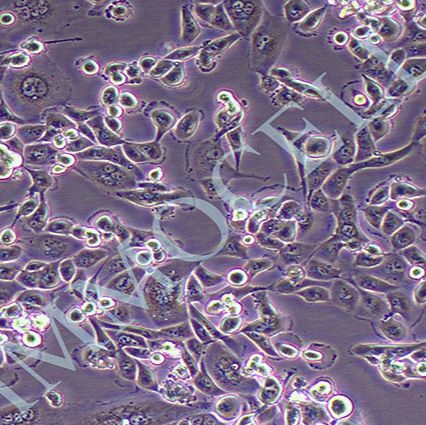

2) 形态:上皮细胞样

3) 含量:>1x106 个/mL

4) 污染:支原体、细菌、酵母和真菌检测为阴性

5) 规格:T25瓶或者1mL冻存管包装